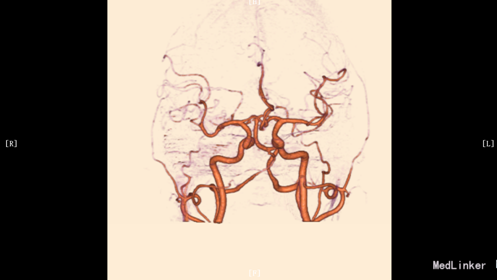

入院体检:T 36.9°C,P 87次/分,R 22次/分,BP 136/69mmHg。全身皮肤无黄染及出血点,全身浅表淋巴结未扪及肿大。双肺呼吸音清,未闻及干湿性罗音。心率87bpm,律齐,各瓣膜听诊区未闻及杂音。腹平,腹肌软,肝脾肋下未及,无压痛、反跳痛,肠鸣音正常。脊柱四肢无畸形,双下肢无水肿。神经系统:神清语晰,对答切题,记忆力、定向力、计算力正常,查体合作。双侧瞳孔等圆等大,直径约3mm,对光反射灵敏,双眼球活动自如,未见眼震。双侧额纹对称,双侧鼻唇沟对称,伸舌居中。四肢肌张力正常,左侧肢体肌力II级,指鼻试验、跟膝胫试验、闭目难立征未能配合检查。双侧腱反射对称存在,双侧巴氏征未引出。颈软,双侧克氏征、布氏征(-)。 辅助检查:生化:超敏C反应蛋白:2.6mg /l、乳酸脱氢酶(LDH):105U/L、甘油三酯(TG):2.32mmol/L、尿酸(URIC):416umol/L;同型半胱氨酸:14.3umol /l;D-二聚体定量:270ng /ml;糖化血红蛋白(HbA1c):5.1%;红细胞沉降率:3mm/h;人脂蛋白相关磷脂酶A2:378ng /ml;风湿十二项:(-); 胸部DR:主动脉硬化,双肺未见异常。心脏彩超:LVEF:66%。心内结构未见异常。 心内未见异常血流。 左室舒张功能降低。颈血管彩超:双侧颈总动脉、颈内动脉、颈外动脉、椎动脉未见异常。 双侧颈动脉、椎动脉血流速度正常。 急诊CT未见明显异常。 头颅MR:1、 双侧额叶软化灶,病灶周边少许胶质增生;2、MRA示未见明显异常。 头颅CTA:双侧颈内动脉虹吸段、双侧大脑中动脉、双侧大脑前动脉及其分支管壁尚规则,管腔通畅未见明显狭窄;右侧椎动脉颅内段管腔较左侧稍细小,余椎动脉、基底动脉及双侧大脑后动脉管腔未见明显变窄。大脑willis动脉环清晰显示,未见明显异常。 头颅CTV:大脑静脉系统上矢状窦、窦汇、横窦、乙状窦、直窦、大脑大静脉和颈内静脉管壁规则,管腔通畅未见狭窄、畸形等异常。 动态心电图示:1.窦性心动过缓;2.偶发室性早搏;3.偶发房性早搏;4.提示不完全性右束支阻滞;5.T波改变(心率快时);6.心率变异性:正常。 脑电图无异常。